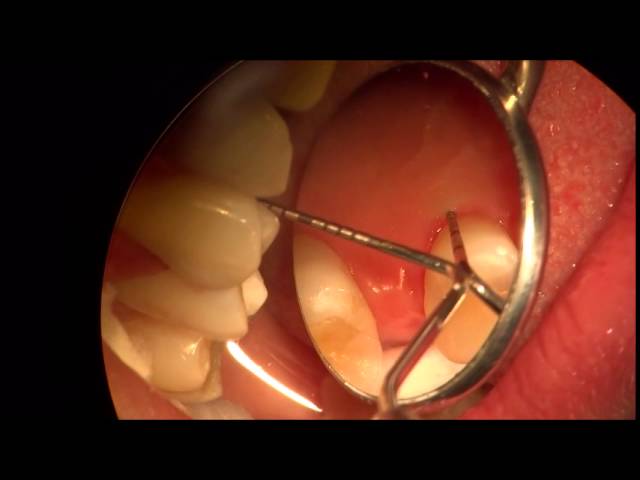

Diagnostico de Fracturas Dentales Verticales

En este video, su autor, nos muestra distintas tecnicas para diagnosticar una fractura dental vertical